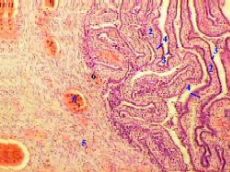

4,а-в. Препарат - яйцевод. Окраска гематоксилин-эозином.

1. На снимках мы видим просвет яйцевода (1) и в нём - многочисленные складки слизистой оболочки (2). 2. а) Складки покрыты однослойным призматическим реснитчатым эпителием (3). б) В толще складок - рыхлая соединительная ткань, составляющая собственную пластинку (4) слизистой оболочки. 3. Основную часть толщины стенки составляет мышечная оболочка (5) из двух слоёв - циркулярного и продольного. 4. Между мышечными пучками идут прослойки соединительной ткани с многочисленными кровеносными сосудами (6). 5. Ещё кнаружи находится соединительная ткань серозной оболочки (7).